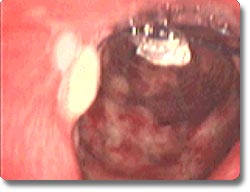

我科于2002年12月24日在麻醉科大力协助下,成功完成西南地区首例通过内窥镜和激光技术进行的颈段气管瘢痕狭窄镍钛合金记忆金属气管支架植入。该患者为一重度闭合脑损伤,瘢痕体质,气管切开术后,不能拔管,辗转数家医院已达半年之久。通过手术一次性关闭气管造瘘口,患者能顺利的经鼻、口自主呼吸,在不给氧情况下,血氧饱和度达到并一直维持在98%以上。这是我科在“十六”大精神鼓舞下,贯彻校、院领导开拓创新的思想指导下,我科在新业务、新技术上取得的又一可喜成果。 |